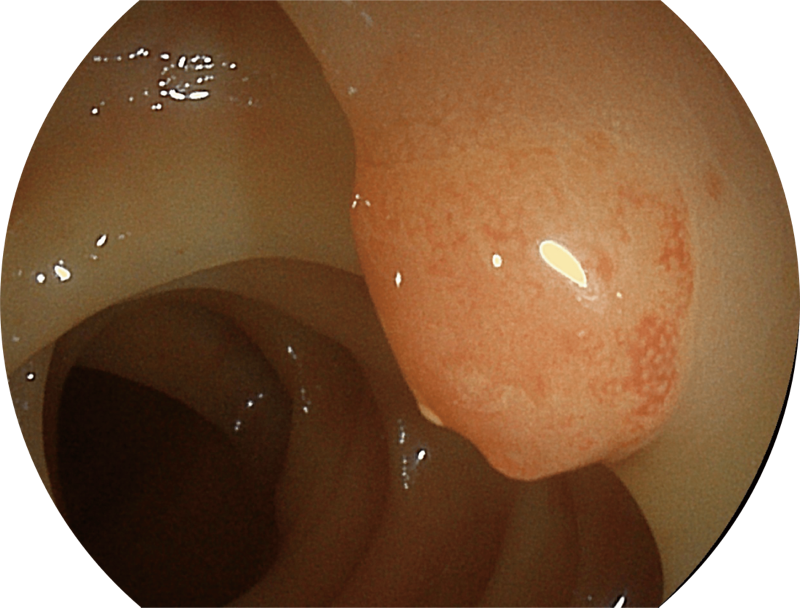

白光图像

SFI图像